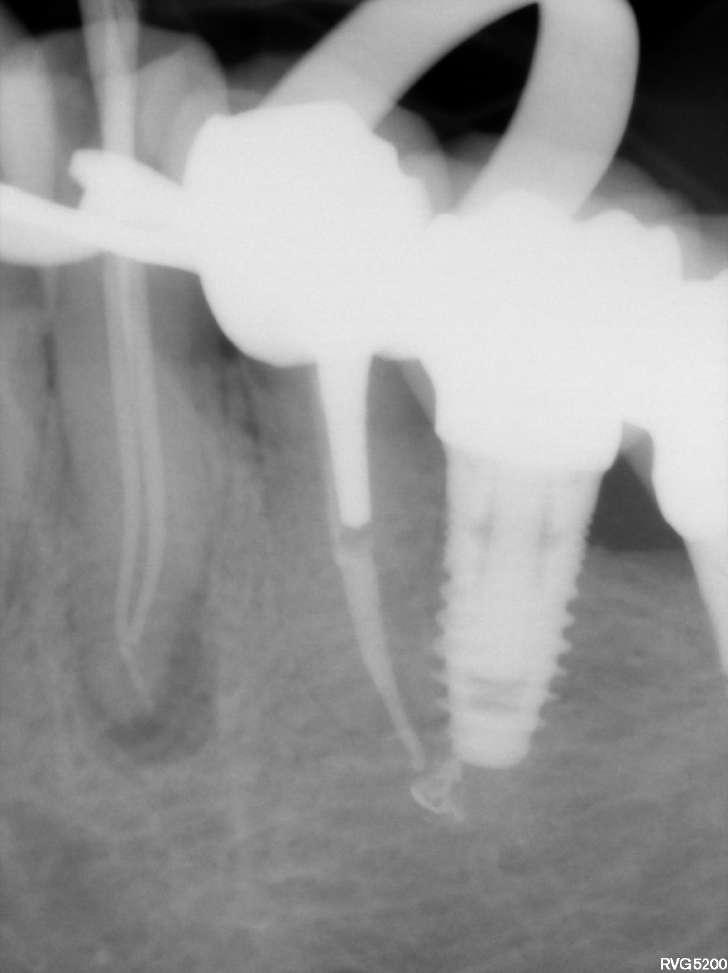

Die endodontische Behandlung fand in einer Sitzung statt. Nach Anästhesie und Anlegen des Kofferdams erfolgte die Entfernung der provisorischen Füllung und die initiale intrakoronale Diagnostik. Mittels Microopener konnte ein mesiobukkaler, mesiolingualer, distobukkaler und distolingualer Wurzelkanal sondiert werden. Die Ausarbeitung der primären Zugangskavität zur besseren Zugänglichkeit der Kanäle erfolgte mit Langschaftrosenbohrern. Anhand des präoperativen diagnostischen Röntgenbilds konnte die Länge der Wurzelkanäle vorläufig näherungsweise bestimmt werden. Die Kanäle wurden im weiteren Therapieverlauf kontinuierlich mit 6% NaOCl gespült. Nach Ausarbeitung der Zugangskavität folgte die koronale Erweiterung der Wurzelkanäle mit EdgeEndo X7 Feilen der Größe 17.06. Die elektrometrische Bestimmung der Kanallänge mithilfe eines Morita Root ZX Mini Apex Locators wurde mit C-Piloten der Größe 8-10 durchgeführt. Nach Festlegung der Arbeitslänge wurde der

Gleitpfad rotierend mit EdgeFile X7 der Größe 17.04 und 25.04 erweitert und final bis auf 30.04 aufbereitet (Abbildung 2).

Abbildung 2: Blick auf das mesiale Kanalsystem nach Präparation